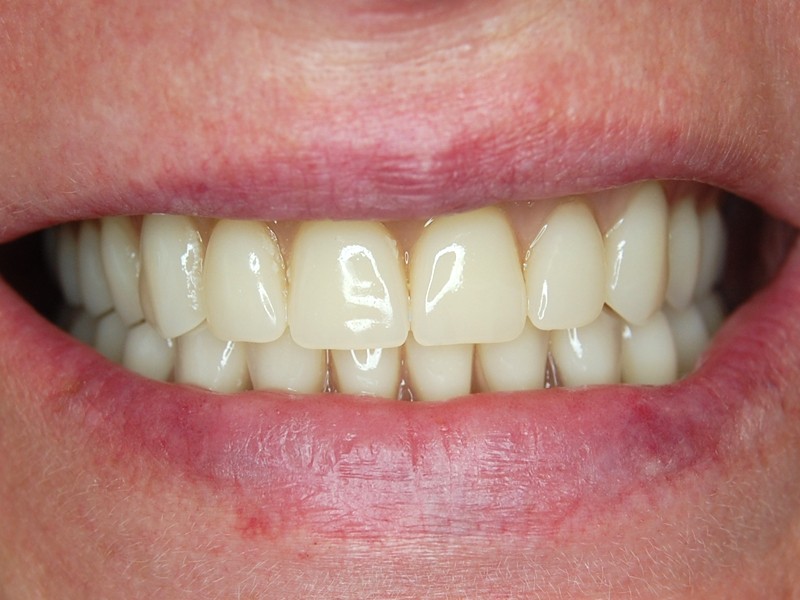

Postup výroby spočíva v CT scane kosti, analýze, digitálnej výrobe 3D modelu kosti, individuálnom nadizajnovaní optimálneho tvaru subperiosteálneho implantátu, ktorý je vyrobený výhradne z bioinertného titánu najvyššej kvality grade 5. Finálny produkt je po povrchovej úprave inzerovaný operačne v lokálnej alebo celkovej anestéze. Pooperačné hojenie sliznice vyžaduje krátky čas ktorý využívame na zhotovenie hybridnej snímateĺnej náhrady podĺa náročnosti pacienta.